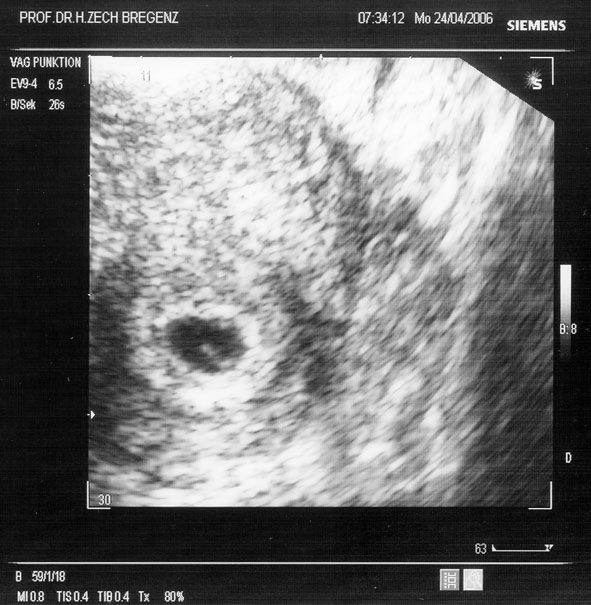

gratulation zu den tollen fotos *neid * jetzt seid ihr wirklich schwarz auf weiss schwanger, wie toll

1. ICSI bei Prof. Zech Bregenz im Februar 2006, Transfer von 2 befruchteten Eizellen - Resultat meine Tochter Finja am 01.12.2006